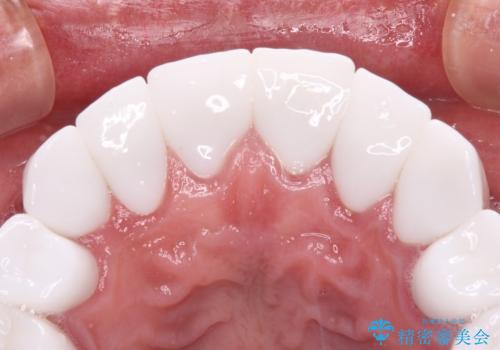

とにかく作り物のような真っ白な歯にしたい フルジルコニアクラウンによる補綴治療

不自然なくらい真っ白にしたいとのことでしたので、透明感のないフルジルコニアクラウンを用いて補綴することとしました。

本来、あまりにも不自然な歯となるため、フルジルコニアクラウンを前歯に使用することは、咬合力が強すぎる場合を除き、ほとんどありません。

それでも、色調、形態ともに不自然なくらい真っ白な歯をご希望でしたので、患者様には大変満足していただきました。